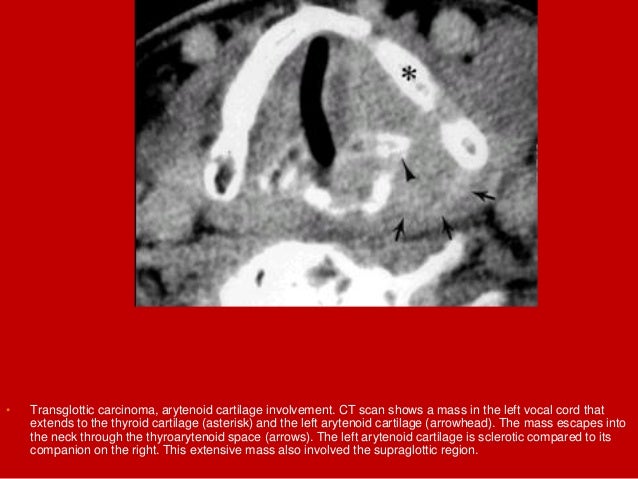

39. 39. • Transglottic carcinoma, arytenoid cartilage involvement. CT scan shows a mass in the left vocal cord that extends to the thyroid cartilage (asterisk) and the left arytenoid cartilage (arrowhead). The mass escapes into the neck through the thyroarytenoid space (arrows). The left arytenoid cartilage is sclerotic compared to its companion on the right. This extensive mass also involved the supraglottic region.